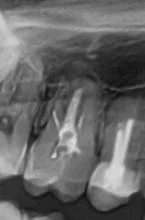

Полгода назад мне сделали пломбу на №2 (с язычной стороны).

Результат - пломба шершавая (что само по себе не гуд),

- появился темный контур вокруг пломбы (появился вторичный кариес, возможно, плохо почистили гнилые ткани),

- с фронтальной стороны тоже просвечивает темное, есть небольшая полость, куда можно залезть иголочкой (то есть, пломба разгерметизировалась, плохо прилегает или дала усадку)

- есть чувствительность на сладкое

- после пломбировки полгода назад сразу была повышенная чувствительность на холодное/горячее и др, врач сказал. что это нормально, надо подождать. А сейчас я пришла к пониманию, что либо плохо промыли водой протравку (кислоту), либо не положили какую-нибудь нужную прокладку типа стеклоиономера (а когда полость близко к нерву-пульпе, говорят, лучше использовать спец. прокладки)

Итог: обидно, за эту работу заплачены деньги. Вторичный кариес - увеличил полость. Такое лечение, наверное, никого бы не устроило.